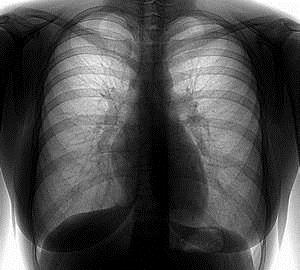

Як зазначалося вище, рентген відрізняється від флюорографії. Остання, проте, виконує ті ж функції - виявляє затемнення і просвітлення на знімках при пневмонії, туберкульозі, пухлинах та ін. Існує, однак, різниця між обома видами променевого дослідження.

Головна відмінність полягає в тому, що флюорографія легень робиться щорічно з метою профілактики населення, тобто цю процедуру повинні проходити всі без винятку.

До недоліків флюорографії можна віднести маленьку роздільну здатність в порівнянні з тією, яку дає рентген, на якому затемнення легенів має більш чітке зображення.